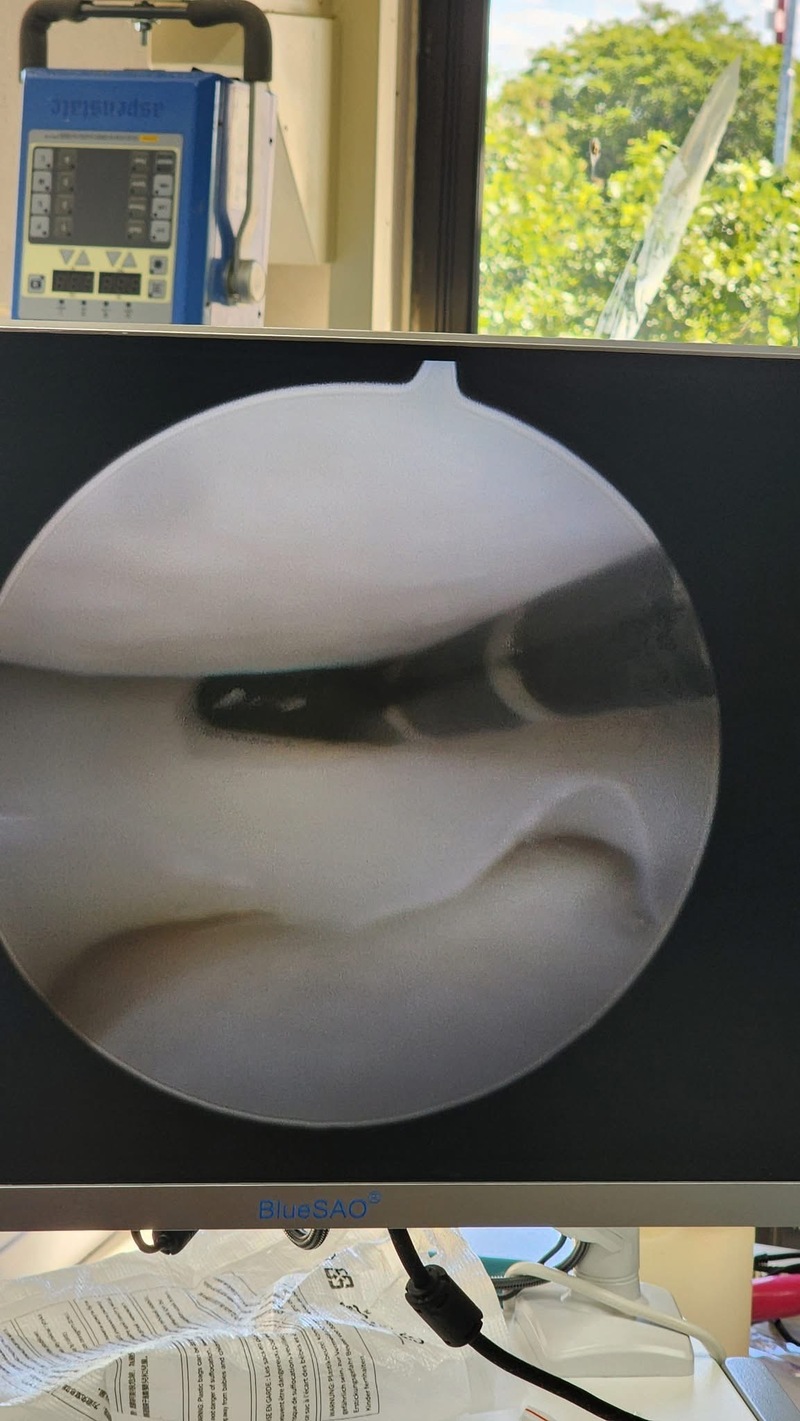

Topic: BlueSAO-Mexico Arthroscopy CourseDate: October 31 - November 1, 2025Location: Mérida, capital of Yucatán, MexicoWhile the BlueSAO Bionic Total Hip Replacement Course at the UC Davis School of Veterinary Medicine (a world-class institution) was kicking off, the first arthroscopy class of Bailu in Mexico was also successfully launched! Special thanks to the renowned Spanish arthroscopy lecturer Dr. Jose Luis Martinez Moran for his brilliant sharing, which combined theory with hands-on practice to provide a feast of knowledge for doctors from across Latin America. During the practical sessions, the Bailu Arthroscopy System, with its clear imaging and excellent operational performance, received high recognition and praise from the attending veterinarians. We truly cherish this affirmation from the clinical frontlines. The participating doctors reported that after completing all courses on elbow, shoulder, and knee arthroscopy, the content was detailed, immediately applicable, and highly beneficial. The success of this training would not have been possible without the meticulous preparation and dedicated efforts of the BlueSAO-Mexico team. Thank you all for your hard work! BlueSAO Bailu, letting the world recognize Chinese small animal orthopedics!